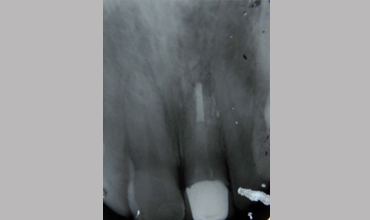

Management Of Fractured Central Incisor With Biological Post